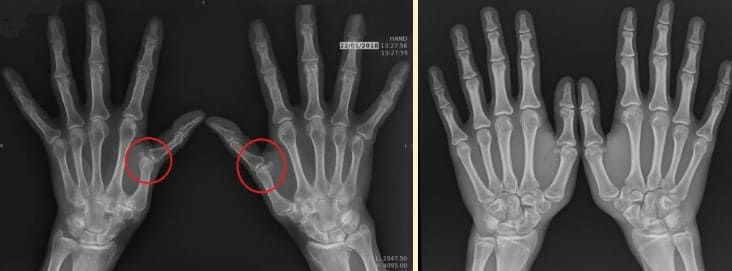

Изследванията в тази област започнаха, когато ревматолози от цяла България публикуваха статистиката на поставените диагнози. Оказа се, че 76% от пациентите на възраст 40 години и повече забелязват проблеми със ставите, тяхната подвижност и гъвкавост.

По време на прегледа откриваме ясни признаци на дегенерация на ставите.

• Медикаментозната терапия с обезболяващи средства наистина премахва неприятните симптоми, но не може да се приема постоянно. При 92% от пациентите бързо се проявяват странични ефекти – връщане на болката и възпалението с удвоена сила, проблеми със сърдечно-съдовата система и храносмилането, и дори повишаване на вътречерепното налягане.

• Физиотерапията може да помогне за намаляване на възпалението на ставата. Могат да са необходими години скъпи процедури: плазмолифтинг, PRP-терапия, вътреставни инжекции и други. Често пациентът пропуска ценно време и рискува да загуби подвижността на ставите завинаги.

• Хирургическата намеса в някои случаи може да бъде ефективна, но самият процес е много болезнен и изисква дълъг период на възстановяване. След такива операции само 6% от пациентите възстановяват здравите си стави.